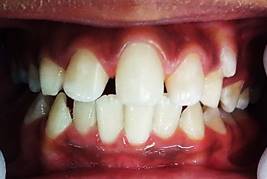

La opción de la ortopedia fue aceptada por la representante del menor y se está a la espera de definir la segunda fase de tratamiento debido al factor económico.

La fase 1 se inició el 8 de junio del 2021, se citó al paciente a controles mensuales durante 6 meses. En diciembre del 2021 se realizó control fotográfico donde se observa disminución en el overjet y overbite, mejora en el perfil y corrección de la mordida profunda (Figuras 5 y 6). Actualmente continúa en seguimiento hasta cumplir el año del tratamiento.